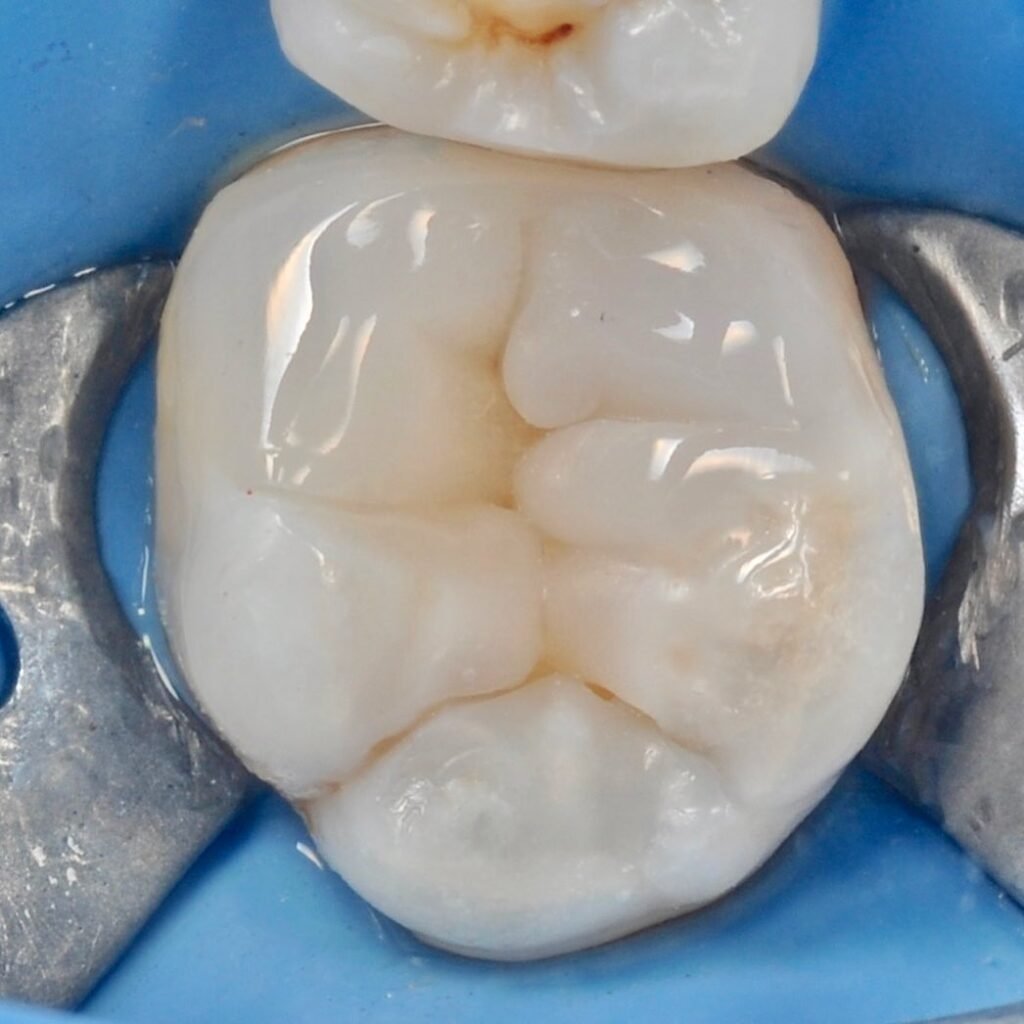

The microscope illuminates and enlarges the working field by about 25 times, which helps to accurately determine the anatomical structure of the tooth and restore it with maximum accuracy.

Dental treatment under a microscope

careful treatment of canals